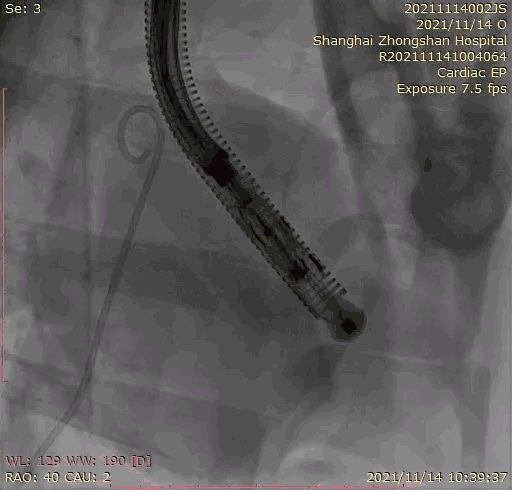

本次臨床前研究經(jīng)右側(cè)頸靜脈置入LuX-Valve Plus輸送系統(tǒng)可調(diào)彎鞘管,在DSA及超聲引導(dǎo)下將人工三尖瓣瓣膜植入到原有三尖瓣位置,利用獨特的錨定技術(shù)將人工瓣膜支架可靠固定在預(yù)定的位置。

上海中山醫(yī)院葛均波院士、錢菊英院長、周達新教授、潘文志教授、潘翠珍教授、李偉教授共同完成此次臨床前研究。術(shù)后葛均波院士對Lux-Valve Plus的器械操作性能給予了高度評價,DSA和超聲影像也顯示出在本次研究中Lux-Valve Plus的安全性和有效性俱佳。